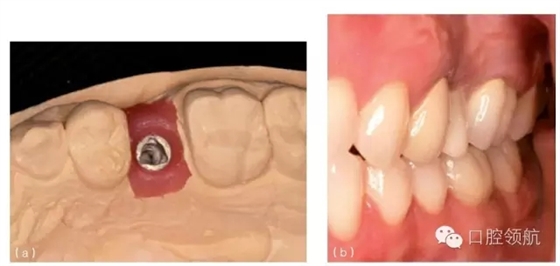

圖10.28 (a)種植體水平印模的模型。注意種植體位于近中稍偏舌側(cè)。(b)為改善頸部外觀,必須采用冠覆蓋頰側(cè)軟組織。(c)全冠要求大量的塑形,并且覆蓋軟組織,以獲得良好的美學(xué)效果。

圖10.29 (a)上頜第一前磨牙種植體位于鄰牙中部近舌側(cè)。(b)冠的牙合面觀,可見牙合面螺絲孔位于冠的舌側(cè)。(c)全冠的唇側(cè)觀,可見大量的烤瓷覆蓋軟組織。